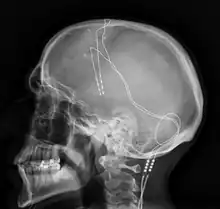

La stimulation cérébrale profonde consiste à implanter des électrodes au niveau des ganglions de la base. Elle a montré des résultats prometteurs[55],[64]. Ce traitement est limité aux formes les plus sévères de la maladie du fait de son caractère invasif et du risque d'infection liée à l'opération.